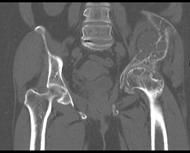

Lezyon; kol ve bacak uzun kemiklerinde, kaburgada, leğen kemiğinde ve kafa-yüz kemiklerinde görülebilir. Monostotik fibröz displazi iskelet sistemi gelişmesi esnasında, poliostotik olanlar ise iskelet sistemi geliştikten sonra ortaya çıkar. Poliostotik olanların %2-3’ü endokrin rahatsızlıklarla birliktedir, ciltte sütlü kahverengi lekelerle birlikte çok kemikte lezyon var ise McCune-Albright sendromu denir. İntramusküler miksoma ile birlikte görülürse Mazabraud Sendromu denir.

Kemikte aşırı zayıflık oluşunca patolojik kırık gelişebilir. Uyluk kemiği üst ucunda lezyonun geliştiği fark edilmez ise çoban asası görüntüsü meydana gelir. Düz grafide buzlu cam görüntüsü tipiktir. Genellikle hastaların şikayeti yoktur. Şişlik ve ağrı şikayeti gelişebilir. Fibröz displazi iskelet sisteminin gelişimi ile birlikte büyür. İskelet büyümesi tamamlanınca lezyonun gelişimi yavaşlar.